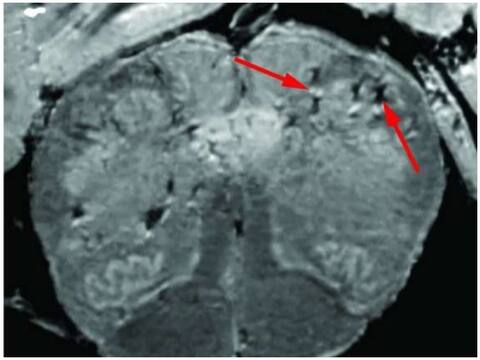

शोधकर्ताओं ने सामान्य एमआरआई से 10 गुना ज्यादा क्षमता वाली संवेदनशील मशीन का हर मरीज के ब्रेन स्टेम और आल्फैक्टरी बल्ब के नमूनों का परीक्षण करने के लिए इस्तेमाल किया. दिमाग के ये दोनों हिस्से कोविड-19 के प्रति ज्यादा संवेदनशील माने जाते हैं. आल्फैक्टरी बल्ब हमारे सूंघने की शक्ति को नियंत्रित करता है जबकि ब्रेन स्टेम सांस और दिल की गति को काबू करता है. स्कैन करने पर पता चला कि दोनों हिस्सों में हाइपरइंटेंसिटिविस नामी चमकीले धब्बों की बहुलता थी जो अक्सर सूजन का संकेत होता है.

इसके अलावा ब्लीडिंग का प्रतिनिधित्व करने वाले हाइपोइंटेंसिटिविस नामी काले धब्बे थे. रिसर्च से खुलासा हुआ कि चमकीले धब्बों में रक्त वाहिका दिमाग में सामान्य ब्लड प्रोटीन के मुकाबले कम पतली थी और उसने इम्यून प्रतिक्रिया पैदा किया. ये धब्बे ब्लड के टी सेल्स और दिमाग के इम्यून सेल्स से घिरे हुए थे. इसके विपरीत, काले धब्बे में दोनों बंद और टपकी हुई रक्त वाहिकाएं थीं लेकिन किसी तरह का इम्यून प्रतिक्रिया नहीं हुआ.